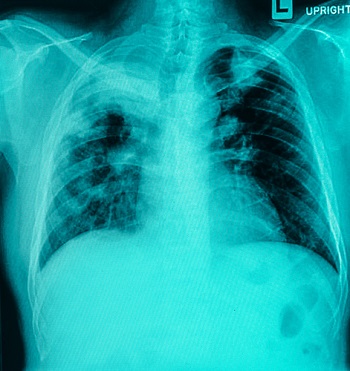

На рентгеновских снимках выявляют следующие признаки, указывающие на спадение легочной ткани:

Однородное затемнение в области поражения. Размеры тени зависят от вида ателектаза: при долевом выявляется обширное затемнение, при сегментарном — в виде клина или треугольника, расположенного вершиной к корню легкого, дольковые ателектазы множественные и похожи на очаговую пневмонию. Дистензионный ателектаз расположен низко, около диафрагмы, имеет небольшие размеры и вид поперечных полос или темных дисков. Смещение органов: при компрессионном ателектазе смещение наблюдается в здоровую сторону, так как на стороне поражения давление больше, при обтурационном, наоборот – смещение будет в сторону ателектаза, так как на стороне поражения нарастает притягивающее отрицательное давление. Подъем купола диафрагмы – это видно по расположению печени.

Если диагноз непонятен, рентгенологическое обследование дополняют компьютерной томографией. При перекрытии просвета бронхов выполняют бронхоскопию – осмотр по ходу бронхов с помощью зонда с камерой, который вводят в дыхательные пути.

Исследование газового состава крови выявляет уменьшение парциального давления кислорода в значительной степени. По этому диагностическому тесту определяют степень острой дыхательной недостаточности, приводящей к тотальной гипоксии.